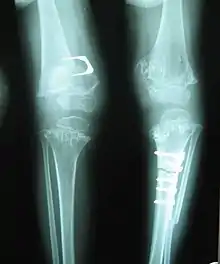

Skeletal radiography

Accurate assessment of plain radiographic findings remains an important contributor to diagnosis of pseudoachondroplasia. It is noteworthy that vertebral radiographic abnormalities tend to resolve over time. Epiphyseal abnormalities tend to run a progressive course. Patients usually suffer early-onset arthritis of hips and knees. Many unique skeletal radiographic abnormalities of patients with pseudoachondroplasia have been reported in the literature.[2][7][4]

- Together with rhizomelic limb shortening, the presence of epiphyseal-metaphyseal changes of the long bones is a distinctive radiologic feature of pseudoachondroplasia.

- Dysplastic/hypoplastic epiphyses especially of shoulders and around the knees.

- Metaphyseal broadening, irregularity and metaphyseal line of ossification. These abnormalities that are typically encountered in proximal humerus and around the knees are collectively known as “rachitic-like changes”.

- Radiographic lesions of the appendicular skeleton are typically bilateral and symmetric.